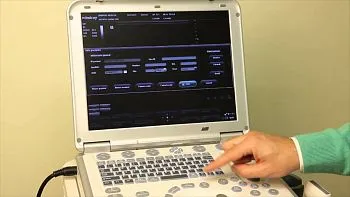

- Настраиваемый пользовательский интерфейс

- Настраиваемый пользовательский интерфейс

Панель управления

Некоторые характеристики консоли

- Сохранение индивидуальных настроек для разных пользователей, использующих аппарат УЗИ.